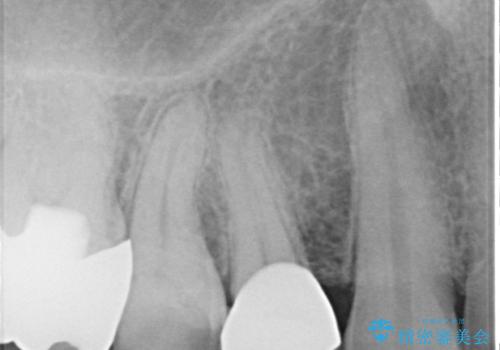

- 食事中に歯が欠けてしまった事を主訴に来院された患者様です。

小臼歯が広範囲に欠けてしまっています。

部分的な詰め物では再びかけてしまうリスクが高いため、オールセラミッククランにて補綴治療をすることとしました。

精度の高い被せものは二次う蝕のリスクが低いです。